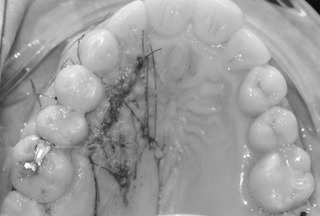

Resultado final (antes-después):